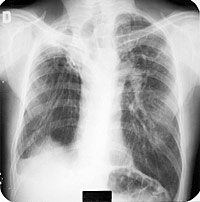

PLACA 40

Comentario placa 40

La arquitectura pulmonar está muy distorsionada con una marcada retracción de ambos lóbulos superiores que arrastra fuertemente a ambos hilios hacia arriba – Los vasos pulmonares se ven casi verticales y los lóbulos inferiores presentan zonas de hipertransparencia por sobredistensión. El hemidiafragma derecho esta oculto por un denso velamiento, probablemente por fibrosis pleural. Todo esto sugiere un proceso cicatrizal importante que, en este caso, corresponde a las secuelas de una tuberculosis bilateral extensa.